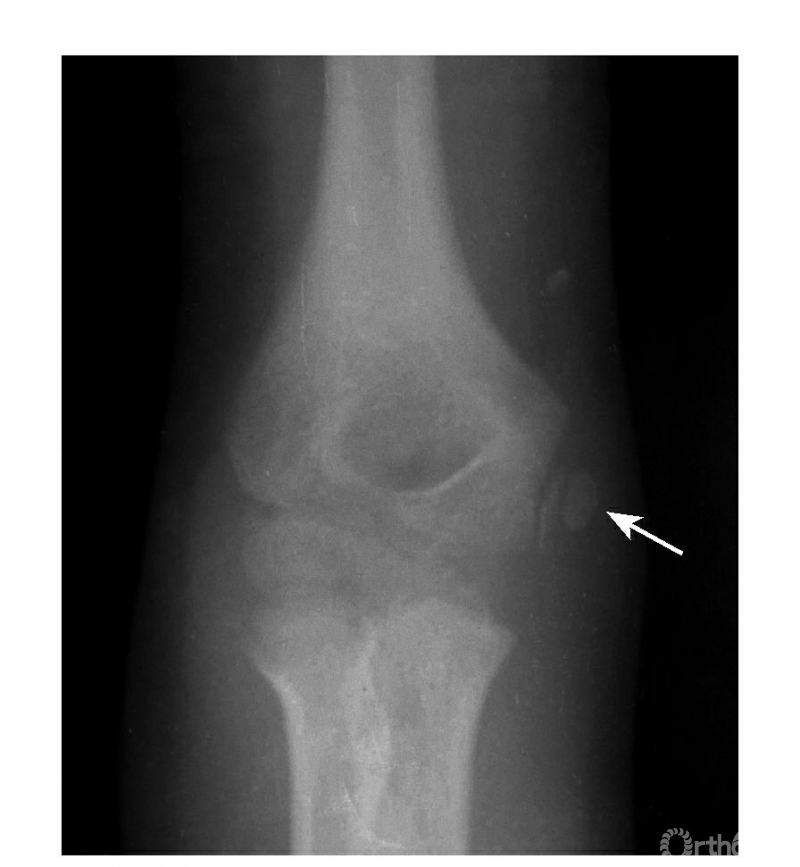

例2:内上髁骨骺并带内髁骨块向外翻转移位,达关节水平(图5)。

图5